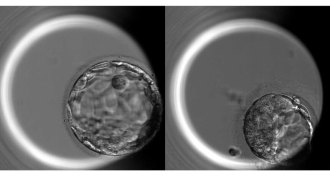

GeneticsGene editing of human embryos gets rid of a mutation that causes heart failure

Gene editing of human embryos can efficiently repair a gene defect without making new mistakes.